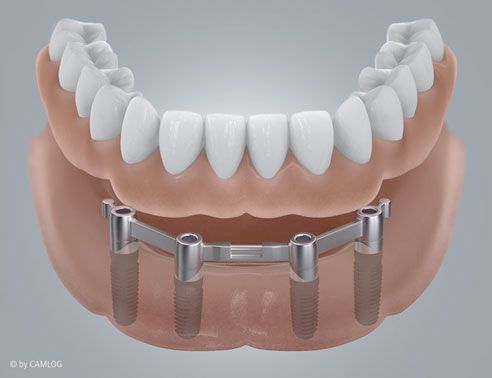

Tipp für Prothesenträger

Mit Hilfe von Mini-Implantaten können wir Vollprothesen im Ober- oder Unterkiefer fixieren. Wenn Sie sich maximalen Komfort im Alltag wünschen, sprechen Sie uns an. Wir beraten Sie gerne.